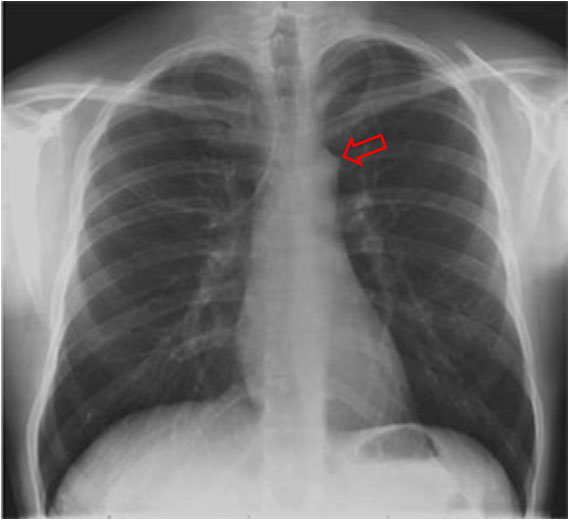

SIGNO DE LA JOROBA DE HAMPTON

Opacidad en cuña con base de contacto pleural, generalmente sin broncograma aéreo, que corresponde a infarto pulmonar. Aunque con frecuencia se localiza en el seno costofrénico lateral, puede encontrarse en otras localizaciones. La fotografía muestra una radiografía PA de tórax donde se observa una joroba de Hampton en el campo medio pulmonar derecho (flecha).